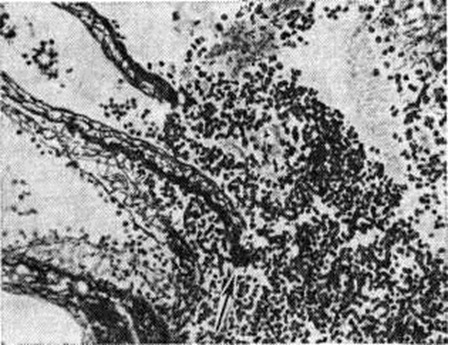

Кровоизлияния типа гематомы сопровождаются образованием полости, содержащей жидкую кровь или свёртки крови; они составляют 85% внутримозговых кровоизлияний, наиболее часто развиваются в подкорковых узлах, реже в мозжечке. Основной механизм развития гематомы — разрыв патологически изменённого сосуда (рисунок 7). Формирование гематомы идёт путём раздвигания кровью вещества мозга с перемещением его участков, что возможно благодаря резервным пространствам (желудочки, подпаутинное пространство). Размеры гематомы при этом превышают объем разрушенного кровью вещества, сдавление окружающих отделов незначительно; лишь при кровоизлиянии в мозжечок сдавление вещества мозга весьма существенно в связи с анатомическими особенностями задней черепной ямки (рисунок 8).

Кровоизлияния типа геморрагического пропитывания возникают преимущественно в зрительных буграх, реже в мосту мозга и составляют 15% внутримозговых кровоизлияний. Они являются результатом слияния мелких очагов кровоизлияний, возникающих путём диапедеза из мелких сосудов, имеют вид очагов красного цвета, дряблой консистенции и в силу внешнего сходства иногда напоминают геморрагический инфаркт. В первые часы Инсульт нарушается проницаемость сосудов на границе с кровоизлиянием, развивается отёк; кровь распространяется по ходу нервных волокон. К концу первых суток наблюдаются лейкостазы и лейкодиапедез, размеры очага увеличиваются за счёт диапедезных геморрагий и некробиотических изменений в отёчном веществе мозга. Через двое суток начинается процесс репарации — появление зернистых шаров и гипертрофированных астроцитов; позже образуется вал из астроглии и новообразованных сосудов, кровь подвергается гемолизу, появляются макрофаги с гемосидерином, образуются аргирофильные и коллагеновые волокна. Исходом кровоизлияния может быть формирование глиомезодермального рубца или кисты, содержащих гемосидерин (рисунок 9). В 80—85% кровоизлияний на вскрытии выявляется прорыв крови в желудочки, значительно реже — в подпаутинное пространство. В последнее кровь может также проникнуть из четвёртого желудочка. Первичные вентрикулярные геморрагии нетравматического генеза — явление казуистическое. При разрыве врождённых аневризм артерий основания мозга возникают первичные субарахноидальные кровоизлияния, которые обычно локализуются на базальной поверхности или в латеральной борозде; иногда кровь проникает в субдуральное пространство; часто повреждается вещество мозга (субарахноидально-паренхиматозные кровоизлияния). Расположение гематом, образующихся при этом, зависит от локализации аневризмы, обычно это базальный отдел лобной доли или височная область. В части случаев при незначительном субарахноидально-паренхиматозном кровоизлиянии возможен массивный прорыв крови в желудочки (рисунок 10), что иногда ошибочно диагностируется как первичное вентрикулярное кровоизлияние.